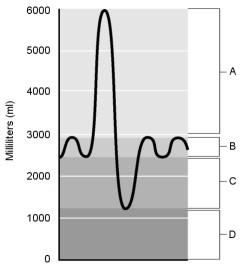

Residual volume.

Air that does not participate in the exchange of gases.